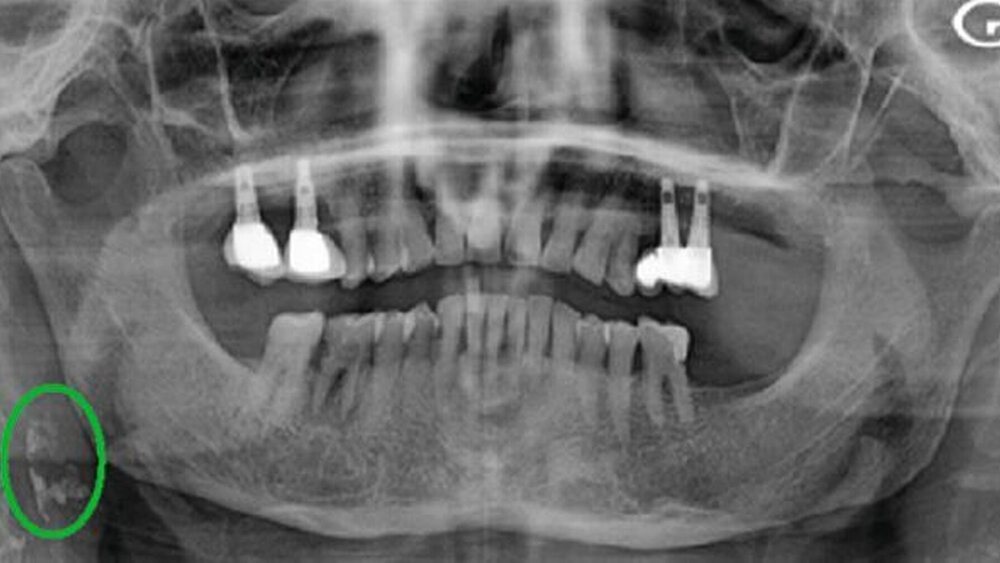

Die Autorinnen und Autoren berichten über eine 70-jährige Patientin, die sich mit dem Wunsch eines Implantats bei ihrem Zahnarzt vorstellte. Sie befand sich bereits aufgrund einer bekannten Hypertonie in kardiologischer Behandlung. Im Rahmen der Implantat-Planung wurde eine Panoramaschichtaufnahme angefertigt und „auf der Ebene der rechten laterozervikalen Region wurden mehrere verschmelzende, heterogene, röntgendichte Bilder von Kalkablagerungen mit unregelmäßigen Grenzen entdeckt, die auf der Ebene der prävertebralen Weichteile zwischen dem zweiten und dem dritten Halswirbel (C2 und C3), hinter dem Unterkieferwinkel, neben dem Zungenbein, hervorstehen und sich vertikal über etwa 16 mm erstrecken“ (Abbildung 1) [Zaghden et al., 2023]. Die Patientin wurde daraufhin erneut bei ihrem Kardiologen vorstellig. Die Doppler-Ultraschall-Untersuchung bestätigte den Verdacht einer atheromatös-kalkhaltigen Infiltration der Arteria carotis interna, aber es war zunächst keine chirurgische Intervention notwendig. Die Patientin wurde medikamentös eingestellt und engmaschig kontrolliert.

In der Panoramaschichtaufnahme können sich Karotisverkalkungen durch röntgenopake Strukturen inferior und posterior des Unterkieferwinkels ungefähr auf Höhe des dritten und des vierten Halswirbelsdarstellen [Zaghden et al., 2023]. Die Plaques können einseitig oder beidseitig auftreten, homo- oder heterogen sein und verschiedene Formen aufweisen. Wichtig ist die Kenntnis möglicher Überlagerungen mit anderen Strukturen sowie Differenzialdiagnosen. Die Autoren nennen als mögliche überlagernde Strukturen „das Zungenbein, Verkalkungen des Triticusknorpels, das Oberhorn des Schilddrüsenknorpels, das Ligamentum stylohyoideum und die Epiglottis“ und als Differenzialdiagnosen „Verkalkungen der Gaumenmandeln, Phlebolithen, Lithiasis der Hauptspeicheldrüsen, Rhinolithen und Verkalkungen der zervikalen Lymphknoten“ [Zaghden et al., 2023].